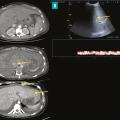

Syndrome de Budd-Chiari

Le syndrome de Budd-Chiari (SBC) est une affection rare caractérisée par une obstruction du drainage veineux hépatique, commençant au niveau des veinules hépatiques jusqu’à la partie terminale de la veine cave inférieure. Il peut se manifester par un tableau d’hépatite fulminante, notamment en cas d’obstruction complète des trois…

Thrombose porte et ischémie mésentérique veineuses

La thrombose de la veine porte (TVP) se caractérise par l’obstruction, le plus souvent par un thrombus, de la veine porte et/ou de ses branches portales (droite et/ou gauche). Cette obstruction peut être partielle ou complète, récente (moins de six mois) ou chronique (plus de six mois) et peut également affecter les vaisseaux…